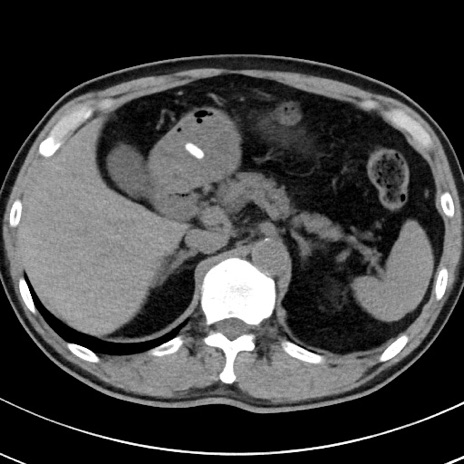

【腹部TIPS】症例29 参考症例 CT(横断像)

症例

70歳代男性